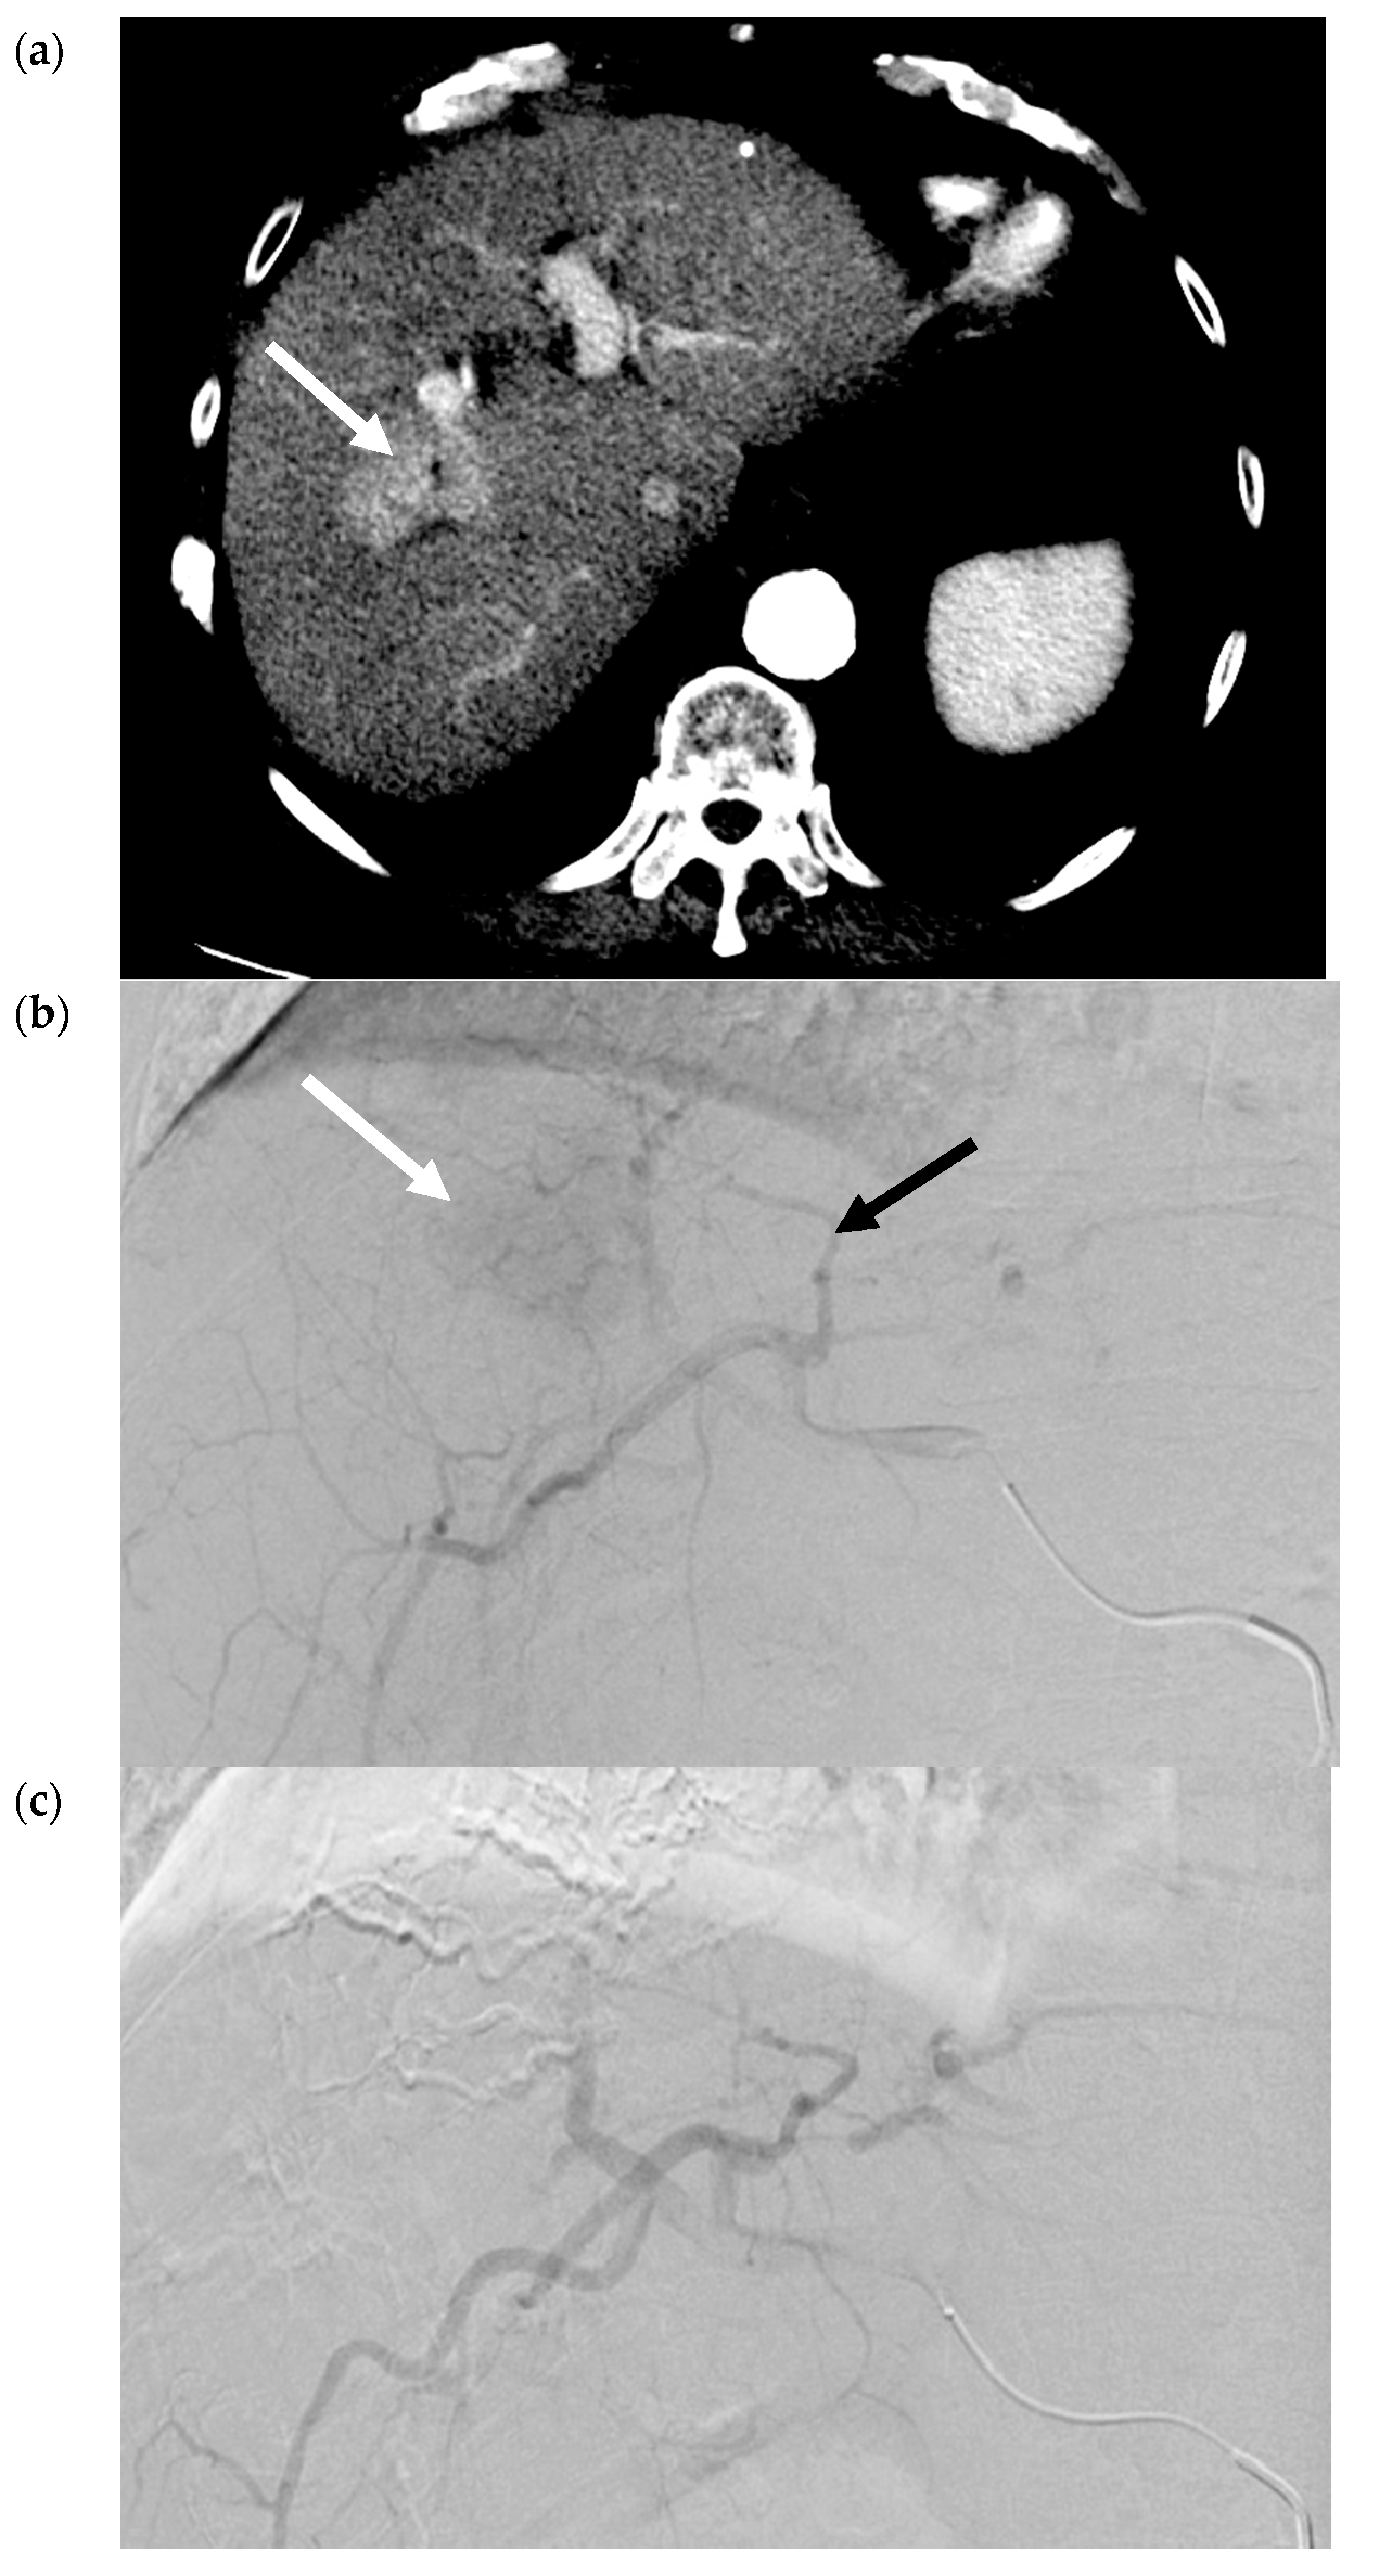

- Riaz, A.; Gates, V.; Atassi, B.; Lewandowski, R.; Mulcahy, M.F.; Ryu, R.K.; Sato, K.T.; Baker, T.; Kulik, L.; Gupta, R.; et al. Radiation Segmentectomy: A Novel Approach to Increase Safety and Efficacy of Radioembolization. Int. J. Radiat. Oncol. 2011, 79, 163–171. [Google Scholar] [CrossRef]

- Padia, S.A.; Kwan, S.W.; Roudsari, B.; Monsky, W.L.; Coveler, A.; Harris, W.P. Superselective Yttrium-90 Radioembolization for Hepatocellular Carcinoma Yields High Response Rates with Minimal Toxicity. J. Vasc. Interv. Radiol. 2014, 25, 1067–1073. [Google Scholar] [CrossRef] [PubMed]

- Lewandowski, R.; Gabr, A.; Abouchaleh, N.; Ali, R.; Al Asadi, A.; Mora, R.; Kulik, L.; Ganger, D.; Desai, K.; Thornburg, B.; et al. Radiation Segmentectomy: Potential Curative Therapy for Early Hepatocellular Carcinoma. Radiology 2018, 287, 1050–1058. [Google Scholar] [CrossRef]